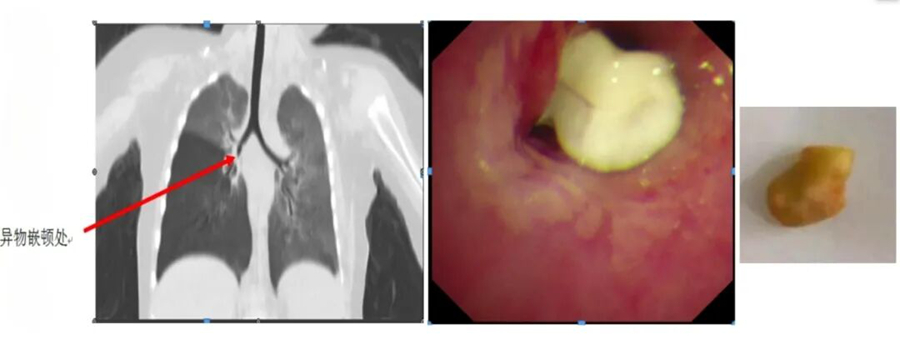

有一名患儿反复“肺炎”半年多,在当地医院多次治疗仍不见好转,家长慕名找到王文棣。她仔细为患儿听诊,敏锐地捕捉到孩子双肺呼吸音左右不对称这一关键线索,通过电子纤维支气管镜检查揪出了“真凶”,竟是半粒花生米堵在了患儿的右主支气管管口。当异物被成功取出后,孩子的 “肺炎”再也没有复发。